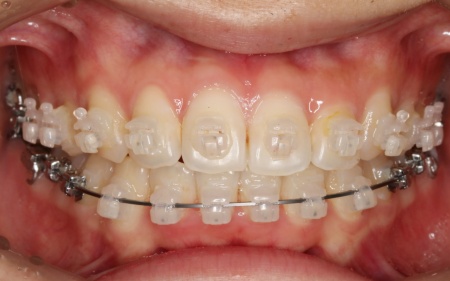

治療中